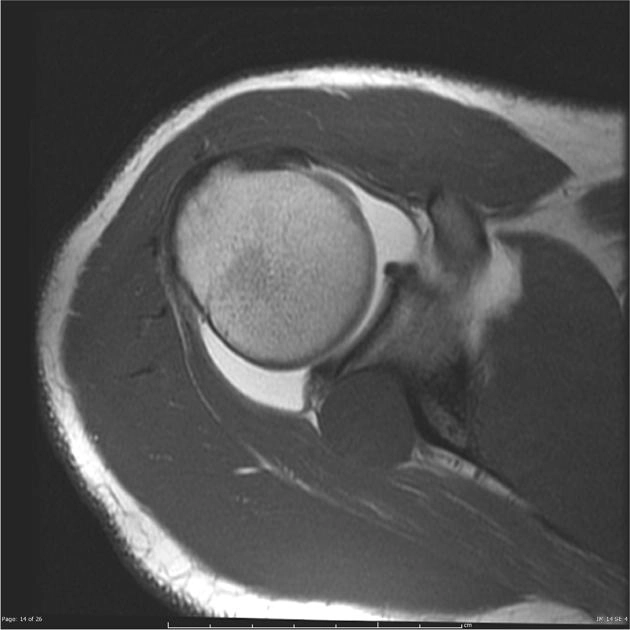

• Nang vai

U nang hạch ở khuyết gai-ổ chảo (Spinoglenoid notch ganglion cyst)

Nang cạnh sụn viền vai (Paralabral cyst of the shoulder)